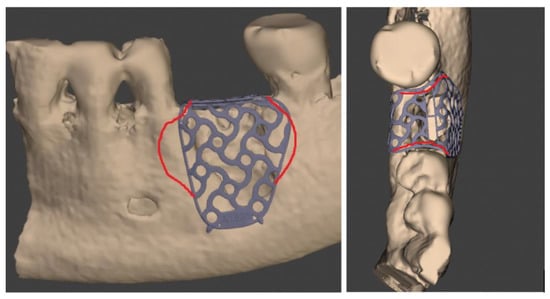

All the enrolled patients received a CBCT scan before CBR (T0): DICOM files obtained were sent to the Master Centre (Yxoss CBR® by Reoss) to share the Ti mesh planning and design. A digital model of the Ti-mesh was provided by the manufacturer for the final approval. Any planned change to the mesh, if necessary, was communicated by clinician to the digital technician to achieve an appropriate mesh morphology (Figure 1).

These screenshots show all the customized Ti mesh changes shared between the surgeon and the digital technician in the pre-clinical digital planning.

After final clinician approval, the custom Ti mesh (class IV titanium) was produced through laser sintering CAD/CAM technology (Yxoss CBR® by Reoss).